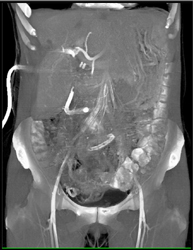

Diagnosis

Normal Hepatic Artery